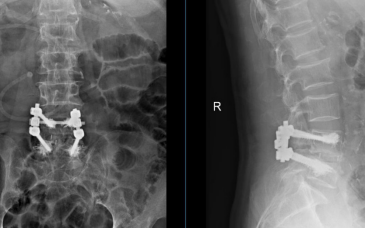

术前X片、CT、MRI

术后X片